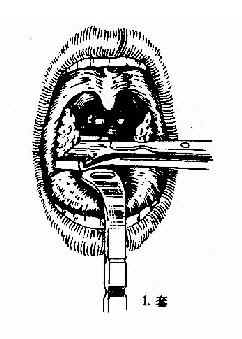

(二)挤切法(guillotine method)(图6-3):

2.操作:病人取仰卧或坐位,助手将其头部固定,置入开口器后,手术者以压舌板压舌,暴露扁桃体下极,右手持挤切刀,从扁桃体下极套入,再转动刀环,使其位于扁桃体和咽腭弓之间,将扁桃体后面及上极套入,并向舌腭弓方向提起,这时扁桃体在舌腭弓下隆起成一“包块”,即用左手拇指或食指将“包块”挤压入环内,随即收紧刀柄,推动刀杆前进,使刀片切入刀环的尽端,以迅速有力的扭转及提拔动作切下扁桃体。以同法切除对侧扁桃体。助手迅速将患者头部侧转,使其将血吐出。止血方法同剥离法。

图6-3 扁桃体挤切术